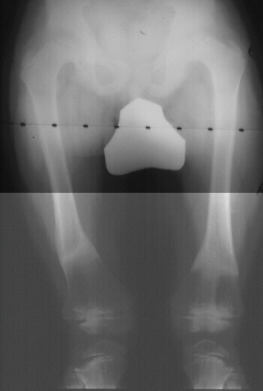

A four year old girl presented for evaluation of short stature. She was the healthy product of a normal pregnancy and delivery. Her height was 80 cm, below the third percentile for her age. Her lower extremities were having mild joint pain and stiffness, she had short stubby hands and feet along with a waddling gait. Limb epiphysis show delayed appearing centers of ossification, often demonstrating a fragmented appearance. Joint involvement is symmetric.

This is best described as an epiphyseal dysplastic process involving all bones.